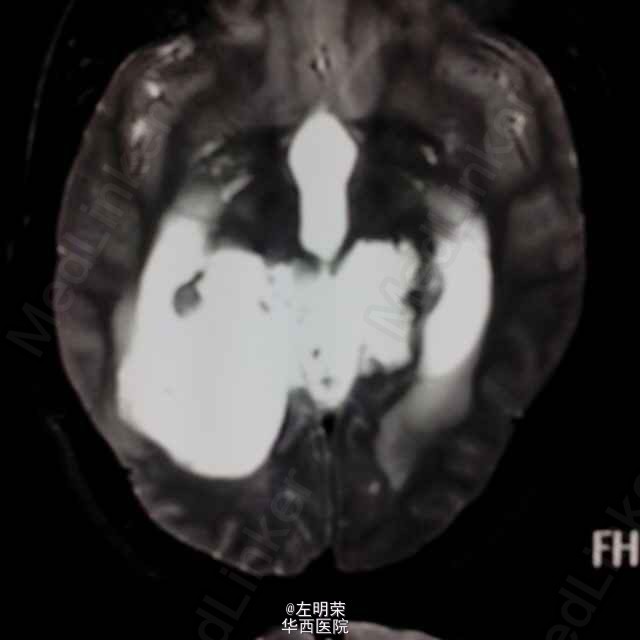

中年男性患者,“反复头痛一年”入院。查体未见明显异常;头部MRI示:松果体区占位,梗阻性脑积水。术中见病变位于右侧脑室三角区,病变范围广泛,侵及丘脑,脑干背侧,松果体区,呈白色珍珠状,质脆,切除过程中出血少,有白色坚韧包膜,予以全切,患者术后恢复良好;病理结果:松果体区表皮样囊肿。